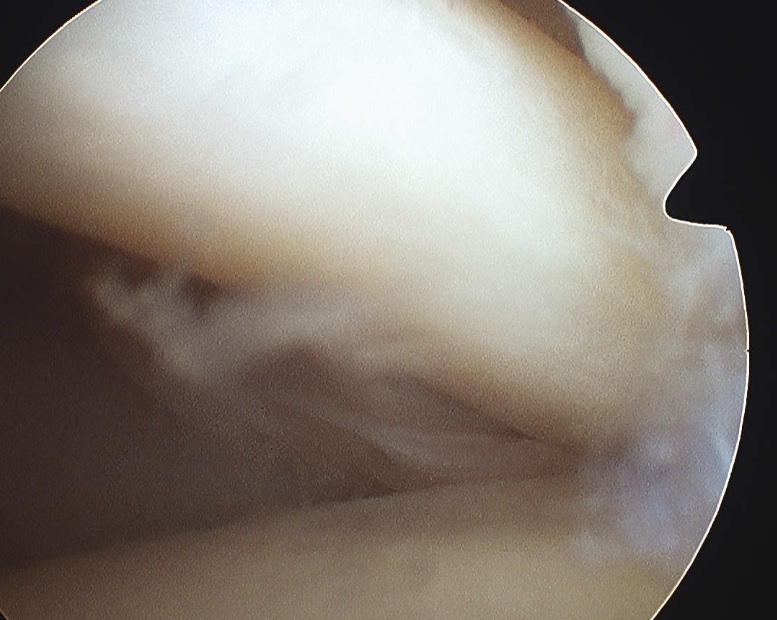

Medial subluxation of LHB